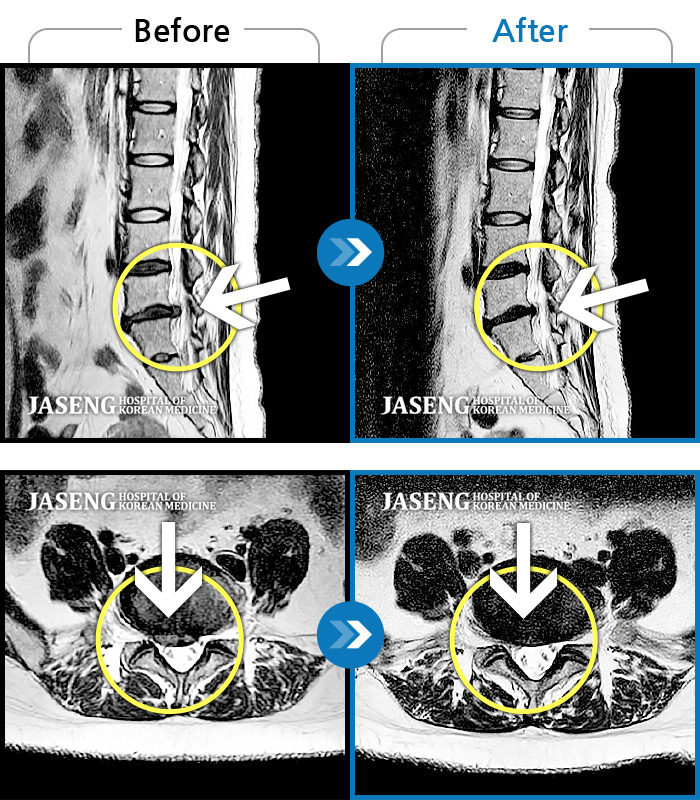

허리디스크

천안 · 윤영웅 원장

허리통증이 심해서 거동이 안돼요.

촬영시기

2021.09.13 ~ 2024.06.11

2024.06.21

조회수 516